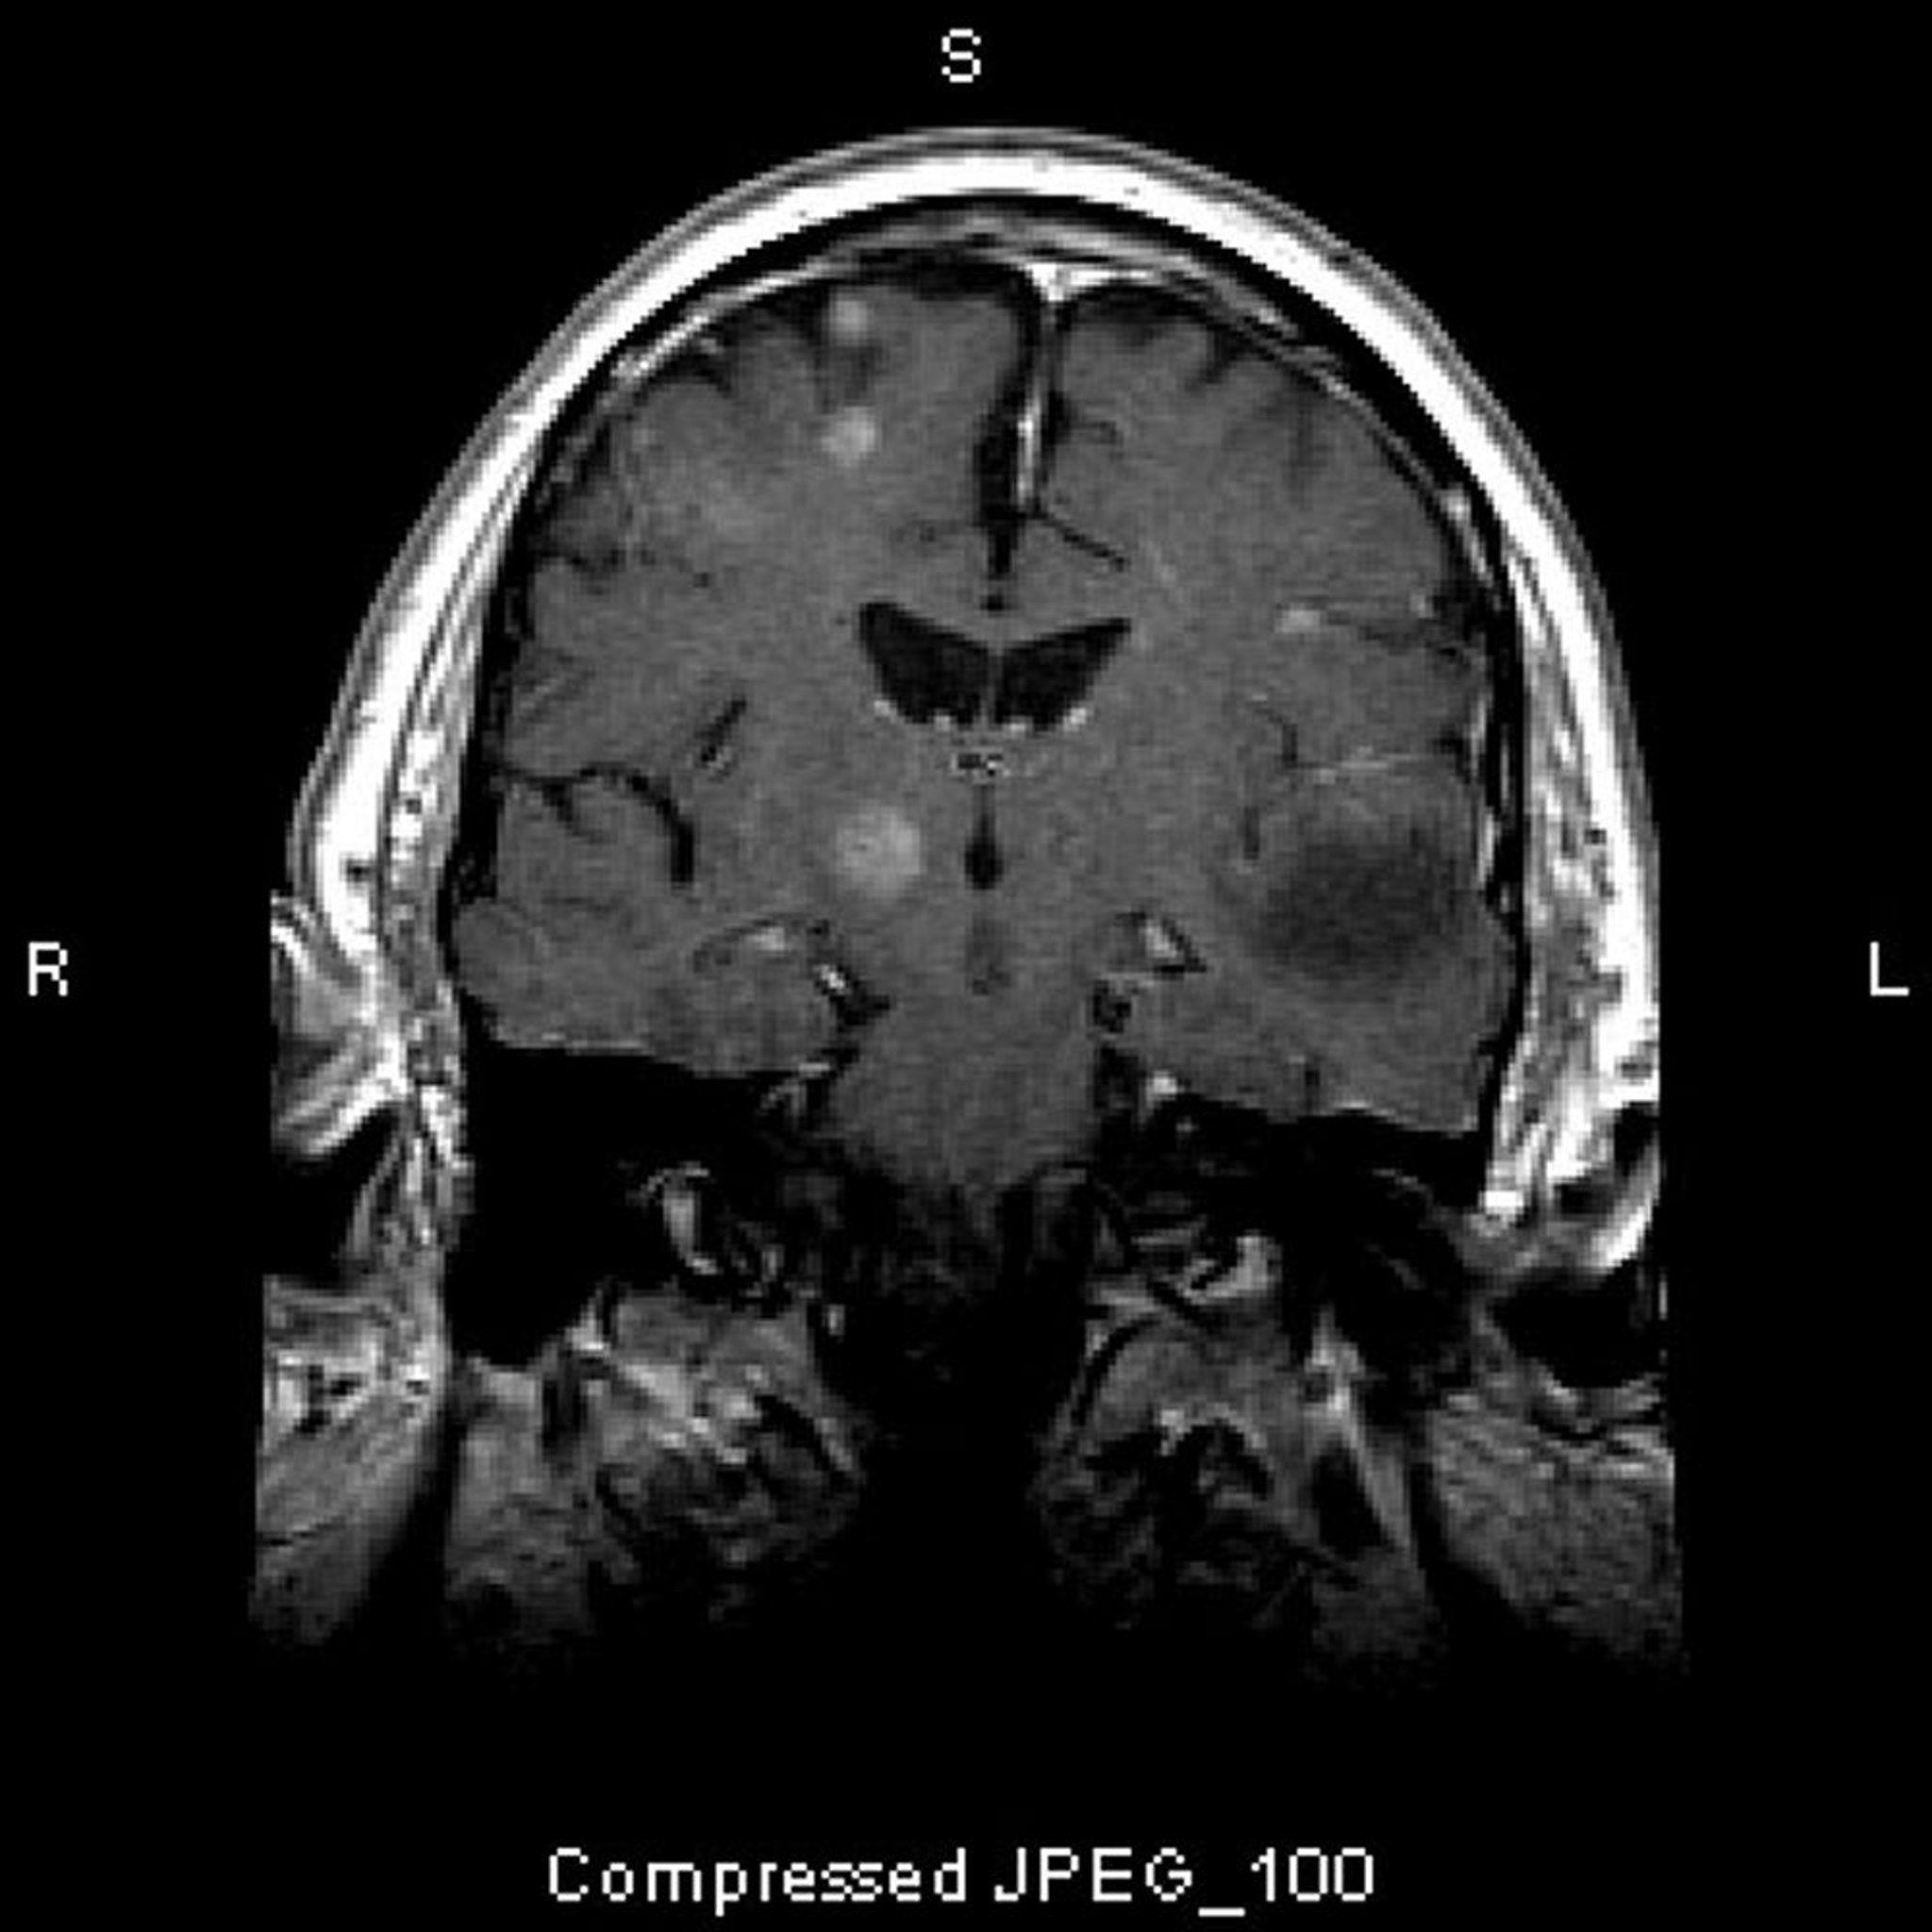

Métastases cérébrales

Cette IRM montre de multiples lésions cérébrales, représentant des tumeurs métastatiques. Plus de 80% des métastases cérébrales sont multiples.

Image courtoisie de William R. Shapiro, MD.